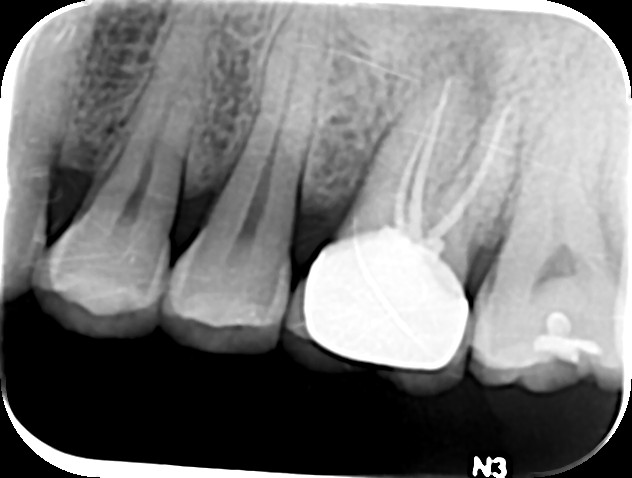

치관확장술의 적용사진입니다.